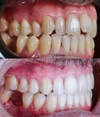

Zirkonyum uygulamalar

Porselen uygulamaları

Laminate veneer